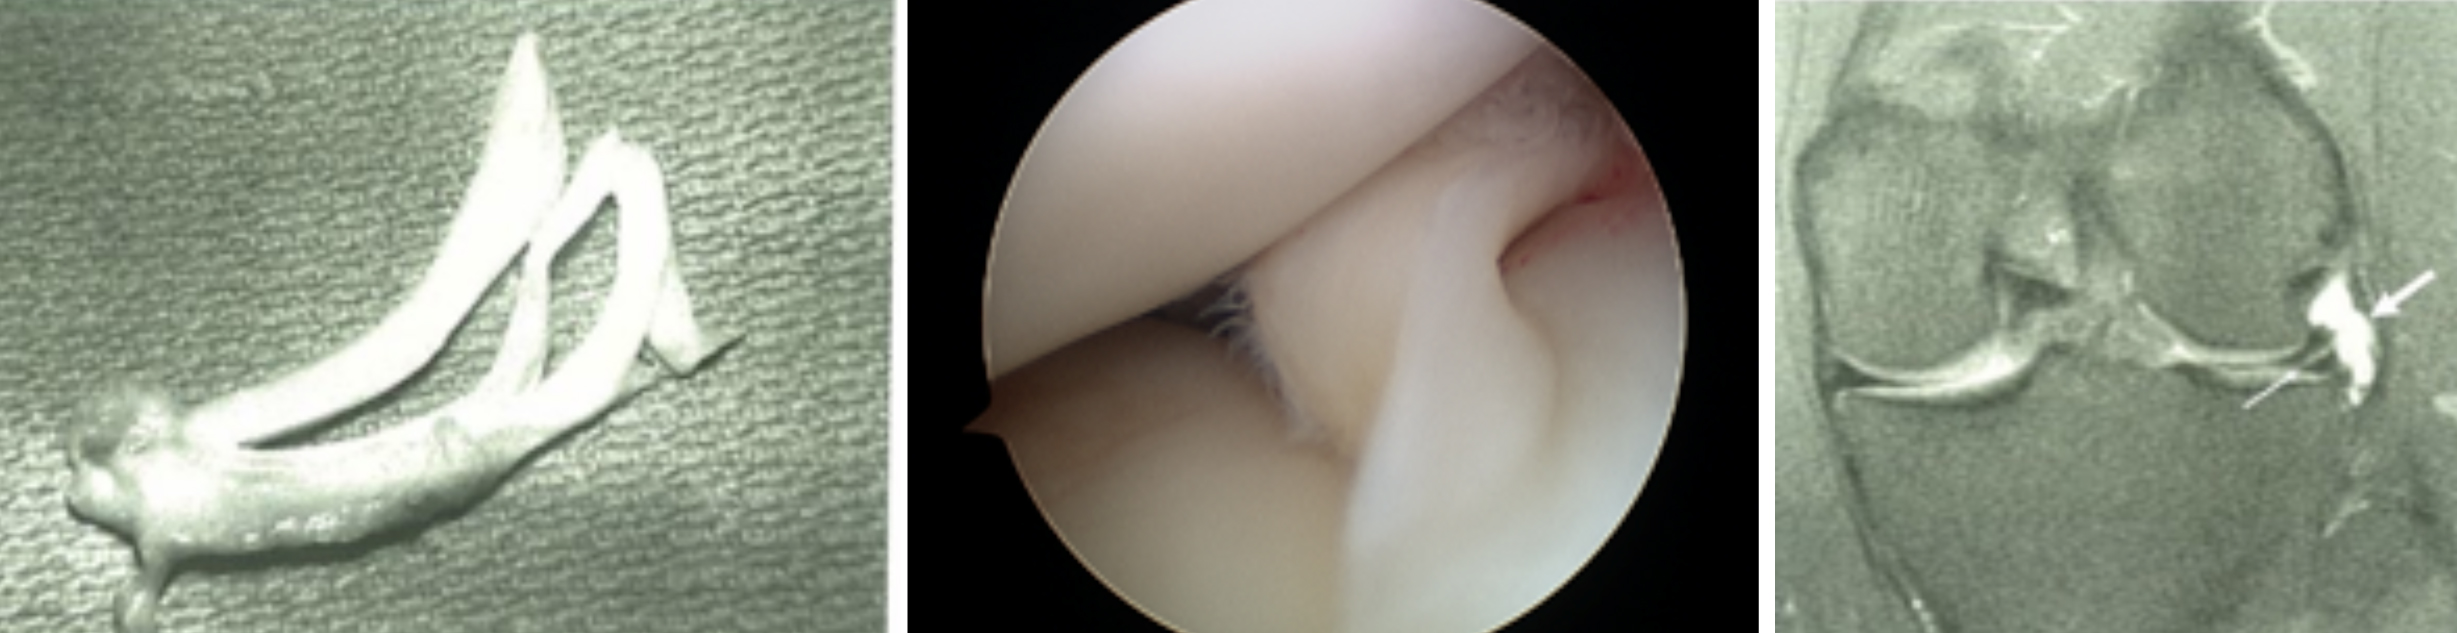

开展关节镜下交叉韧带单、双股解剖重建技术、膝关节多韧带损伤的一期修复重建术、半月板缝合技术、骨软骨移植技术、同种异体移植治疗交叉韧带损伤、双隧道重建交叉韧带、肩关节镜下肩袖修补和SLAP损伤修补术,及肘、踝、腕、髋关节镜术。专业运动员伤病诊治技术、股骨髋臼撞击综合症、股骨头坏死阶梯治疗技术、骨软骨移植技术

关节镜清理、软骨移植修复

膝关节镜-半月板损伤

膝关节镜-前交叉韧带重建

膝关节镜-关节内游离体